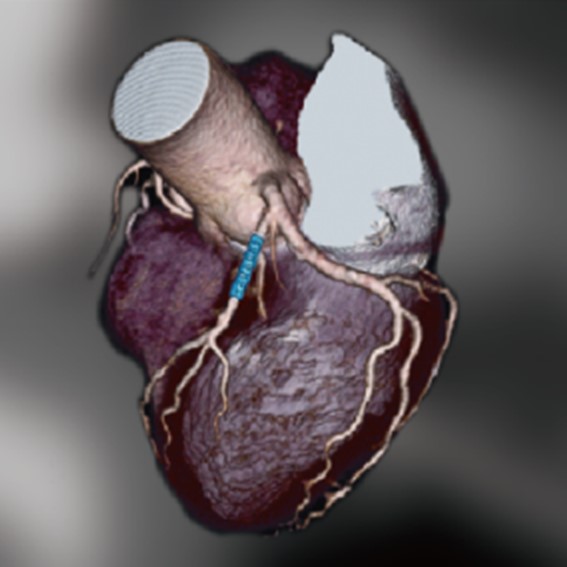

運用高科技尖端影像設備,提供貴賓精準的檢查、判讀、即時醫療、後續追蹤、健康管理或醫學中心轉介服務;從健檢診斷到後端治療,一條龍式服務。永越自成立以來,已服務超過16萬人次,每年通報件數超過千件,揪出包括:甲狀腺癌、肝腫瘤、肺癌、乳癌、子宮頸癌等重大異常的健康警訊,把握住早發現早治療的黃金關鍵。